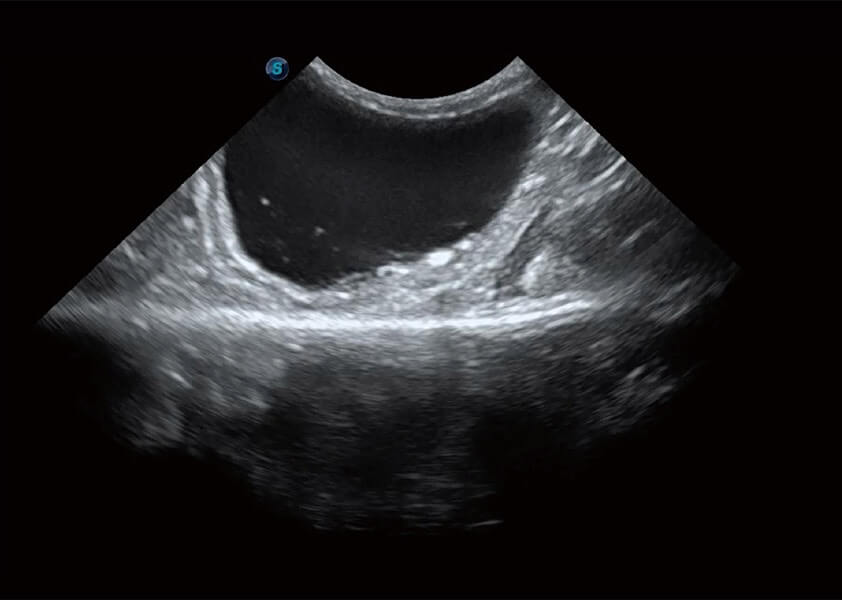

ProPet 60 作为一款高端台式动物超声设备,为动物医生的日常诊断提供了一系列贴合动物临床需求、解决临床实际问题的高级成像功能。凭借全系列高清探头,满足医生对腹部、心脏、生殖、浅表、肌骨等成像的所有需求,切实帮助您提升检查效率,提高诊断信心。

兽用彩色多普勒超声诊断系统

动物是人类最亲密的朋友和最值得信赖的伙伴。百老汇电子游戏官网也一直致力于探索动物专用的超声影像解决方案。 全新推出的ProPet系列,是百老汇电子游戏官网在动物超声影像智能化、专业化、精准化的一次跨越式革新。动物不能用言语来表述自己的不适,通过超声影像,ProPet系列搭建了动物医生与不同物种沟通的“桥梁”,为动物医生注入了“治愈之力”。